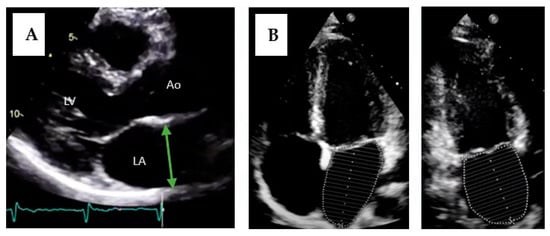

5.1. Diagnosis